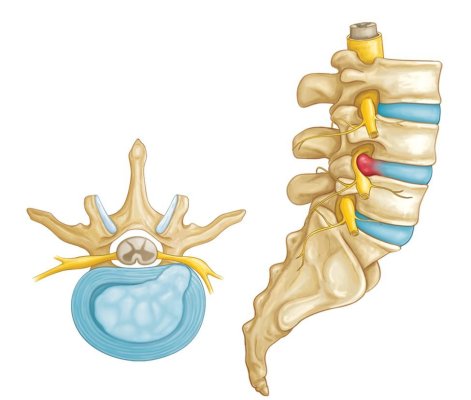

Čo je degeneratívne ochorenie platničiek?

Degeneratívne ochorenie platničiek je najčastejšou príčinou bolestí krížovej chrbtice a bolestí krku, a taktiež jednou z najviac nepochopených chorôb. Jednoducho povedané, degeneratívne ochorenie… Viac

Ako nás platnička začne bolieť

Každá platnička je jedinečná a veľmi dobre navrhnutá štruktúra v našej chrbtici. Je dostatočne silná na to aby ustála ohromné sily v rôznych pohybových rovinách, no pritom je stále veľmi dobre… Viac